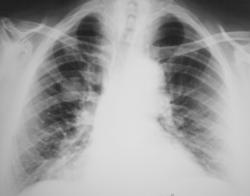

Периферический рак правого лёгкого с метастазами в лимфатические узлы средостения и ребра.

Периферический рак правого лёгкого.